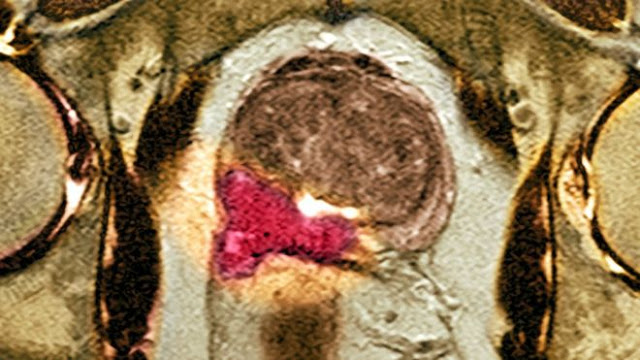

Using MP-MRI to triage men might allow 27% of patients avoid a primary biopsy and diagnosis of 5% fewer clinically insignificant cancers. If subsequent TRUS-biopsies were directed by MP-MRI findings, up to 18% more cases of clinically significant cancer might be detected compared with the standard pathway of TRUS-biopsy for all. MP-MRI, used as a triage test before first prostate biopsy, could reduce unnecessary biopsies by a quarter. MP-MRI can also reduce over-diagnosis of clinically insignificant prostate cancer and improve detection of clinically significant cancer.

93% of aggressive cancers were detected by using the MRI scan to guide the biopsy compared with just 48% when the biopsy was done at random.

The trial, at 11 hospitals in the UK, used multi-parametric MRI on men with high PSA levels.

It showed 27% of the men did not need a biopsy at all.